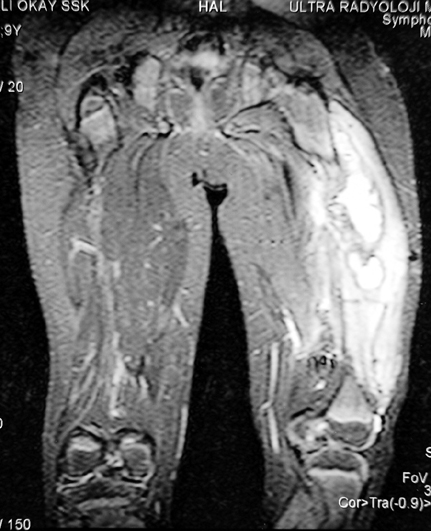

Kronik osteomiyelit, kemik ve yumuşak dokularda nekroza yol açar. Ölü kemik, patojen mikroorganizmalara ev sahipliği yapan bir nidus oluşturur. Konağın savunma sistemleri, mikroorganizmalarla baş etmek için sıklıkla optimal koşullarda değildir. Dolaşım bozukluğu yüzünden enfeksiyon bölgesine antibiyotikler yeterince ulaşamaz. Bu nedenle ölü dokuların ortamdan tamamen uzaklaştırılması gerekir (radikal debridman).

Uygun radikal debridman tüm nekrotik kemik ve yumuşak dokuların çıkartılmasını gerektirir, ve sıklıkla uzuvda instabiliteye neden olur. Kalan kemik ve yumuşak doku defektinin bir şekilde fiksasyonu ve rekonstrüksiyonu gereklidir. İlizarov’un ortaya koyduğu distraksiyon osteogenezi yöntemi, kaynamanın elde edilmesi, deformitenin düzeltilmesi, bacak boy eşitsizliğinin giderilmesi ve segmental defektlerin rekonstrükte edilmesi için başarıyla kullanılmaktadır.